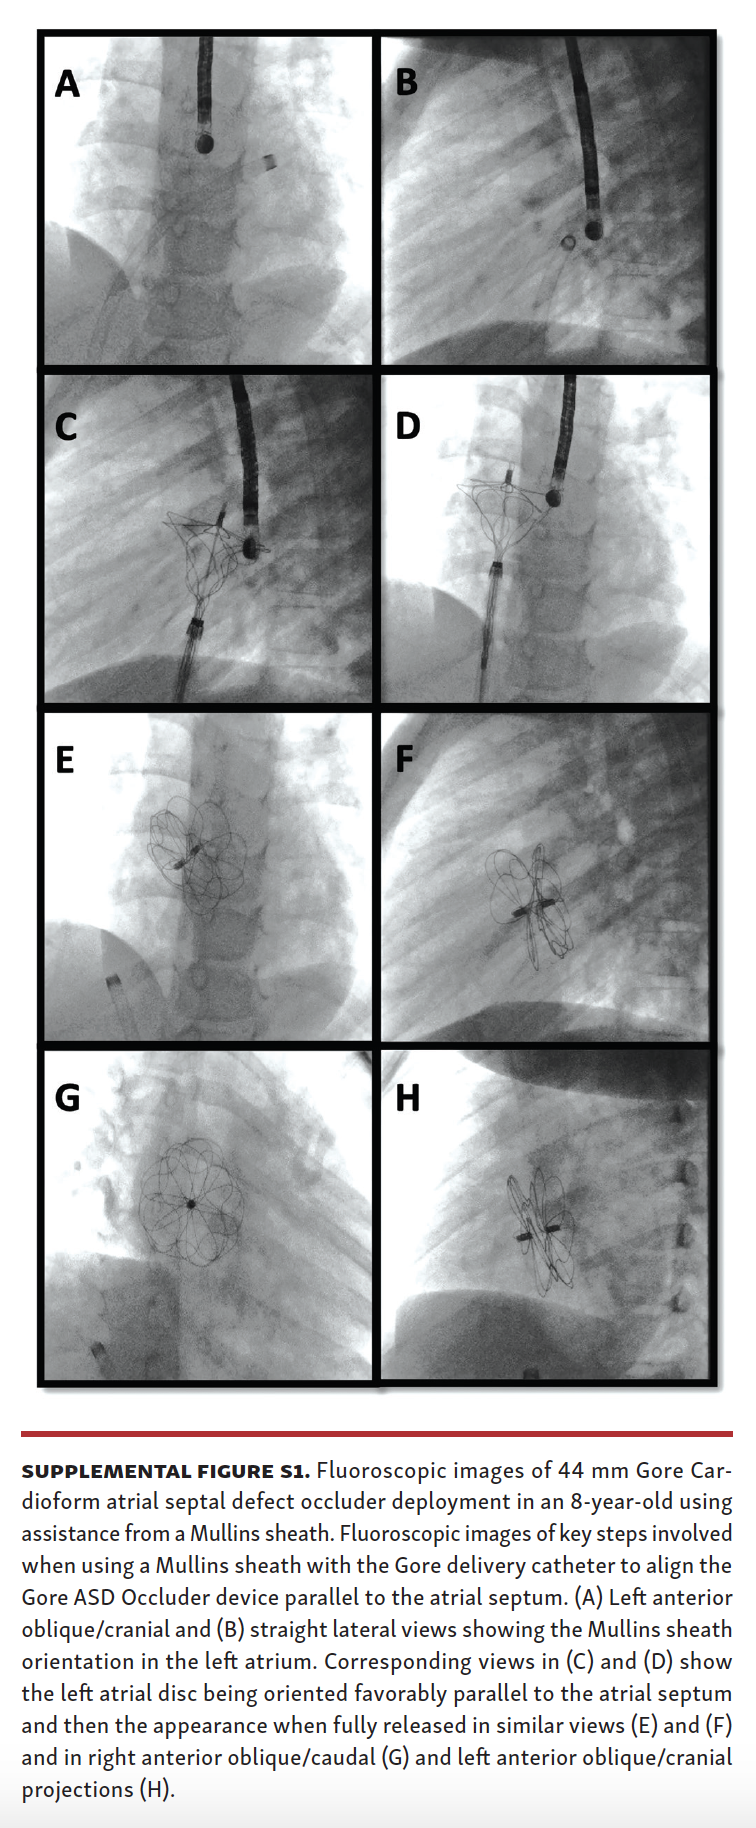

MullinsSheath Facilitated Delivery of Gore Cardioform ASD Occluder Asd Device Closure Technique percutaneous device closure is now the preferred approach for the majority of secundum asds. For most individual patients with. extensive experiences have verified safety and usefulness of the procedure, and established general. device closure of atrial septal defect (asd) important information for patients on what to expect from the asd procedure. It is also a viable. . Asd Device Closure Technique.

MullinsSheath Facilitated Delivery of Gore Cardioform ASD Occluder Asd Device Closure Technique percutaneous device closure is now the preferred approach for the majority of secundum asds. For most individual patients with. extensive experiences have verified safety and usefulness of the procedure, and established general. device closure of atrial septal defect (asd) important information for patients on what to expect from the asd procedure. transcatheter device closure of asd. Asd Device Closure Technique.